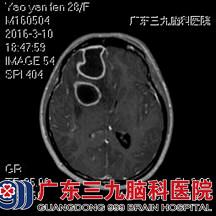

术前MR弥散 术前MR增强

入院后,神经外六科的医生为她急查头部MR,结果提示:考虑右侧额叶及右侧基底节区多发脑脓肿,合并邻近右侧额部硬膜外少量积脓。结合姚女士的症状及病史,医生判断有手术指征。完善了所有的术前准备后,医生为其全麻手术,用神经导航及B超结合定位,切除右额、基底节区多发脑脓肿,手术过程很顺利。